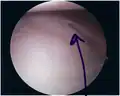

Bankart lesion seen at arthroscopy

Bankart lesion seen at arthroscopy -